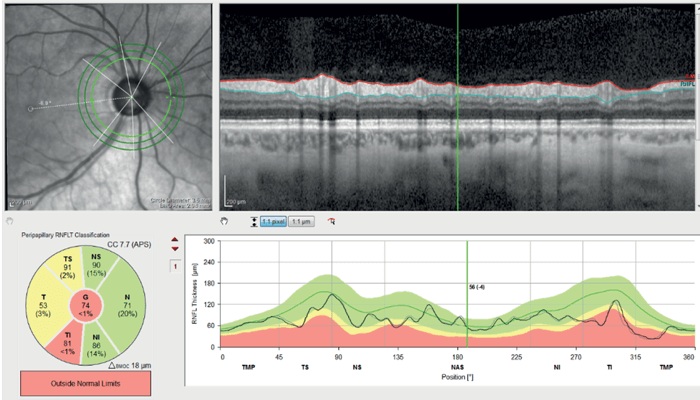

Optical Coherence Tomography Retinal Nerve Fiber Layer (OCTRNFL) with the SPECTRALIS platform (Heidelberg Engineering) revealed temporal thinning in the right eye, more in the inferotemporal quadrant (see Figure 2). Glaucoma causes retinal thinning and asymmetry in the macula (specifically in the ganglion cell layer), so we assessed OCT Macula which revealed relative asymmetry and thinning inferiorly (see Figure 3). Ganglion Cell Layer segmentation revealed generalized thinning and asymmetry between the superior and inferior hemifield.

OCT-RNFL in the left eye showed only mild thinning inferotemporally (see Figure 4) and OCT Macula showed asymmetry of retinal thickness with inferior thinning (see Figure 5).